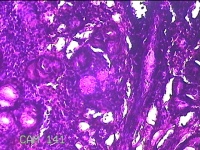

左侧鼻腔病变组织

性别

男

年龄

28岁

临床诊断

1.慢性鼻窦炎 2.鼻中隔偏曲 3.变应性鼻炎

一般病史

反复鼻塞10余年,加重伴脓涕3天。

标本名称

大体所见

灰白暗红色组织0.8x0.3x0.2cm一块,表面糜烂,内有少许骨质。